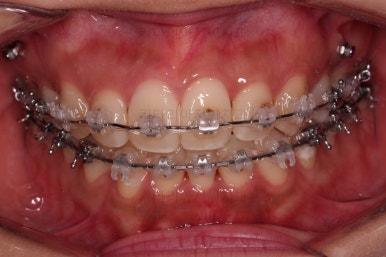

초진 시 입안의 모습입니다.

그냥 봐도 뭔가 애매함이 있죠?

중앙선이 맞지 않고, 교합이 떠보이는 양상이네요.

윗니는 좌측 작은 어금니가 한 개 모자랐고 아랫니는 앞니 하나가 모자라네요.

그런데 앞니는 아랫니가 1개 모자란 채로 교합이 맞춰져서 윗니가 하나 부족한 채로 애매한 상태였어요.